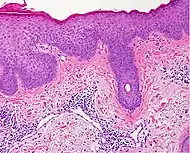

Spongiotic dermatitis

It is characterized by epithelial intercellular edema.[2]

In addition to above, an unspecific spongiotic dermatitis can be consistent with nummular dermatitis, dyshidrotic dermatitis, Id reaction, dermatophytosis, miliaria, Gianotti-Crosti syndrome and pityriasis rosea.[2][notes 2]